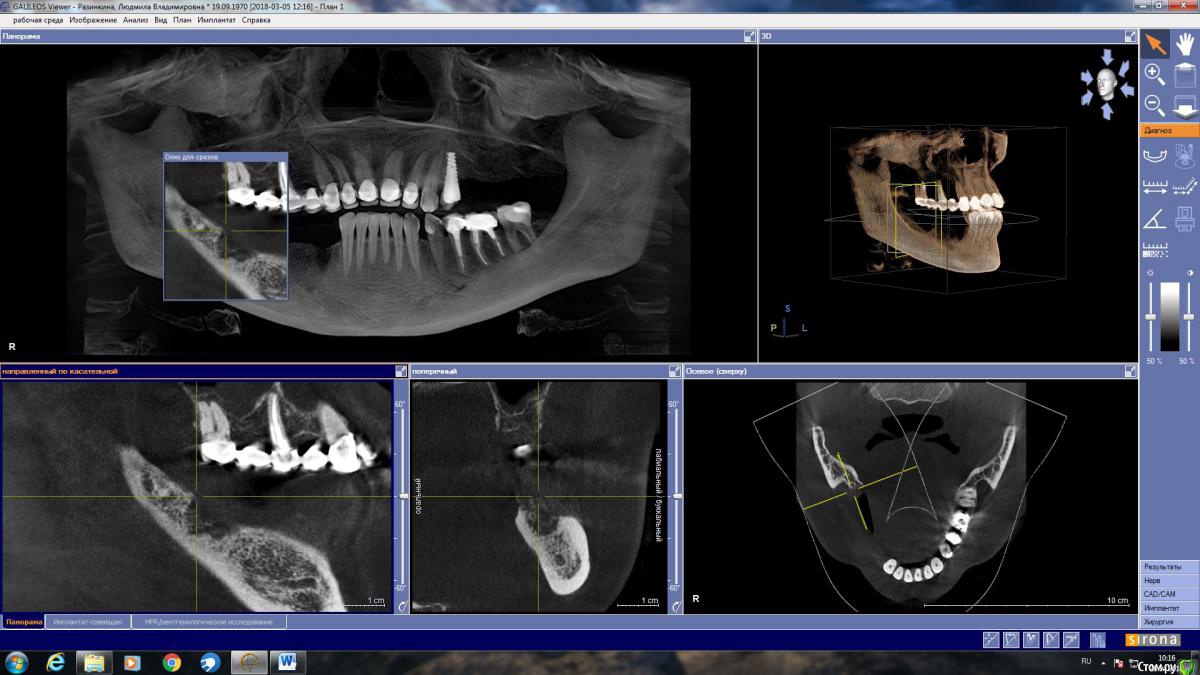

LjudmilaRaz Опубликовано 27 апреля, 2018 Поделиться Опубликовано 27 апреля, 2018 Здравствуйте! Напишите, пожалуйста, своё мнение. В первую очередь планирую имплантацию снизу справа!Обращалась на консультацию к трем врачам. Первый имплантолог предложил нарастить кость и установить четыре импланта. Врач работает только с имплантами одной фирмы (немецкие). Смутило, что полгода назад вариант был совершенно другой и еще то, что очень дорого.Второй предлагает нарастить кость и установить имплант Астра на месте удаленной в декабре четверки со смещением ближе к месту пятерки, и имплант Анкилоз на месте семерки со смещением к шестерке. То есть, накрыв мостом, получится не четыре, а три зуба.Такой же вариант, но с южно-корейскими имплантами (работаю только с ними), предложил третий имплантолог. Это относится к случаю, когда если двое говорят разное, то стоит послушать третьего ? Ссылка на комментарий

LjudmilaRaz Опубликовано 10 мая, 2018 Автор Поделиться Опубликовано 10 мая, 2018 Здравствуйте!С врачом определилась, опытный ЧЛХ стоматолог-имплантолог, еще раз сходила на консультацию. Он считает, что в моем случае более щадяще будет использование костной пластины животного происхождения, которая, становясь после определенных манипуляций пластичной, обогнет с обеих сторон в районе 4 и 5 снизу справа, где в дальнейшем планируется установка двух имплантов (плюс еще один в районе 7-ки - в итоге 3 штуки). По его мнению, ранее им планируемое расщепление в моём случае может стать по факту невозможным, из-за анатомически неблагоприятной ситуации - мало кости. Есть место (практически 2 мм) где при рассечении кость может "съесться" инструментом.Только в моей голове всё сложилось, и тут новый виток. Что думаете про такой способ костной пластики для моего случая. Ссылка на комментарий